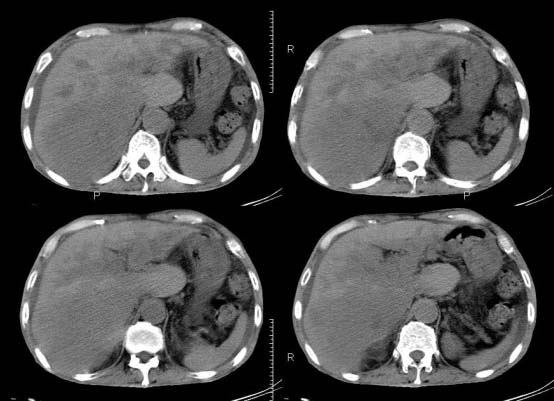

以下是引用杀毒软件在2010-3-30 18:11:00的发言:[br]考虑---hcc侵犯侵犯周围组织〔胰腺、胆管、肠系膜上动静脉〕伴门脉、下腔静脉癌栓形成、动-静脉瘘、肝门、腹腔动脉周围淋巴结转移可能性大、腹水。

以下是引用pujunzhi在2010-3-31 8:45:00的发言:[br]支持 肝癌并多发肝内转移,胰头、肝门、腹腔动脉周围淋巴结转移,下腔静脉癌栓形成,肝硬化、腹水。

以下是引用jsgdoctor在2010-3-30 20:42:00的发言:[br]考虑---hcc侵犯侵犯周围组织〔胰腺、胆管、肠系膜上动静脉〕伴门脉、下腔静脉癌栓形成、动-静脉瘘、肝门、腹腔动脉周围淋巴结转移可能性大、腹水。